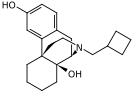

- 3-Hydroxymorphinan

- Cyclorphan

- Levargorphan

- Levorphanol

- Levophenacylmorphan

- Levomethorphan

- Methorphan (racemethorphan)

- Morphanol (racemorphanol)

- Norlevorphanol

- N-Methylmorphinan

- Oxilorphan

- Phenomorphan

- Proxorphan

- Ro4-1539

- Stephodeline Xorphanol

Structures

| Other morphinans | ||||

|---|---|---|---|---|

4-chlorophenylpyridomorphinan 4-chlorophenylpyridomorphinan |

Cyclorphan Cyclorphan |

Dextrallorphan Dextrallorphan |

Levargorphan Levargorphan |

Levophenacylmorphan Levophenacylmorphan |

Levomethorphan Levomethorphan |

Norlevorphanol Norlevorphanol |

N-Methylmorphinan N-Methylmorphinan |

Oxilorphan Oxilorphan |

Phenomorphan Phenomorphan |

Dextromethorphan Dextromethorphan  levomethorphan levomethorphan |

Morphanol Morphanol |

Ro4-1539 Ro4-1539 |

Stephodeline Stephodeline |

Xorphanol Xorphanol |